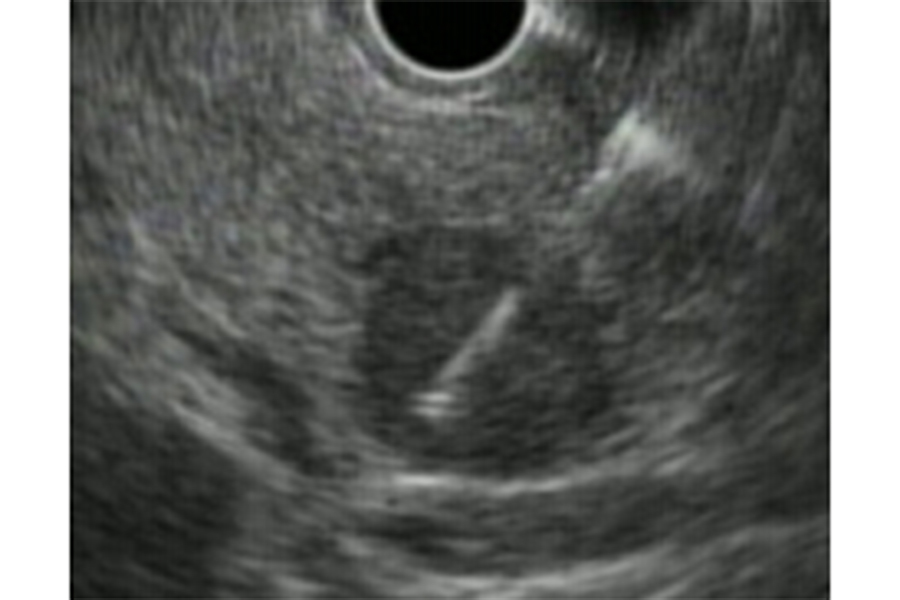

超音波内視鏡(EUS)とは、超音波装置の付いた内視鏡のことであり、“胃カメラ”と同じように口から内視鏡を挿入し、消化管の中から超音波検査を行うことで、空気の影響が少ない状態で、対象臓器・病変の近くで観察することが可能となります。そのため、体外式超音波(US)では十分な観察が難しい胆管や膵臓、通常の内視鏡では詳細がわからない消化管粘膜下病変の詳細な観察が可能であり、それらの臓器や病変に対する精密検査として行います。EUSは、小さな膵癌の描出に有効であり、今後ますます、その役割が重要になってくると考えます。

超音波内視鏡(EUS)は、胃や十二指腸の中から超音波を用いて、膵臓全体を詳細に観察することのできる検査です。我々は、膵のう胞が初めて見つかった際には、

写真は、膵のう胞(黄色矢印)を初めて指摘されてEUSを行い、膵癌(赤矢印)を診断した症例です。